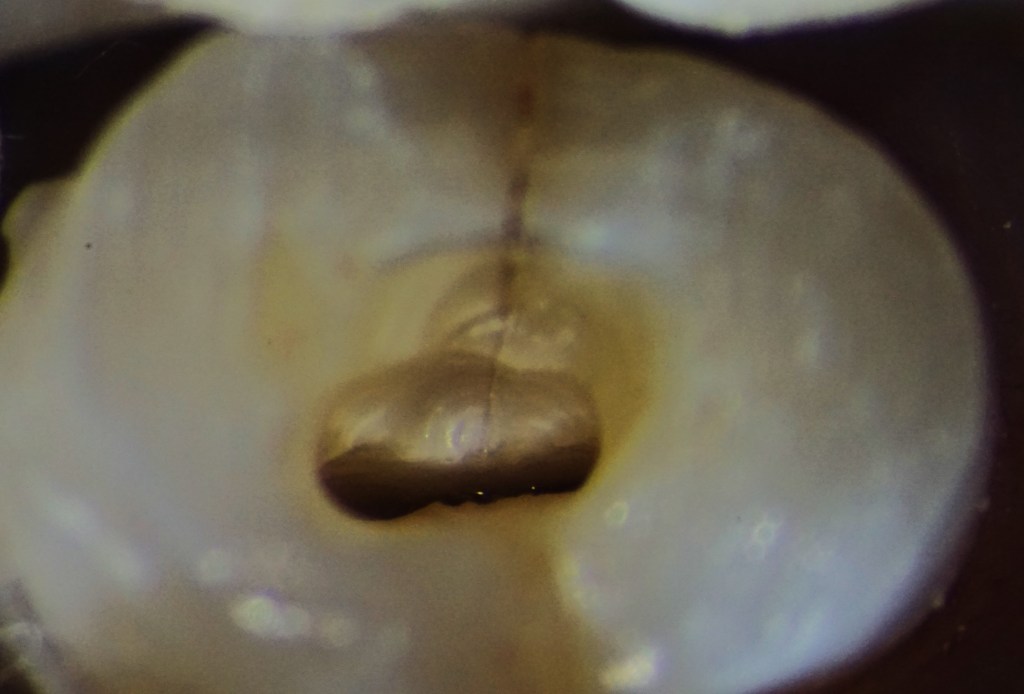

1. központi barázdában szétrepedt fog 2. ugyanezen fog idegkamrájának feltárása után a repedés mélysége is láthatóvá válik (kedvezőtlen prognózis)